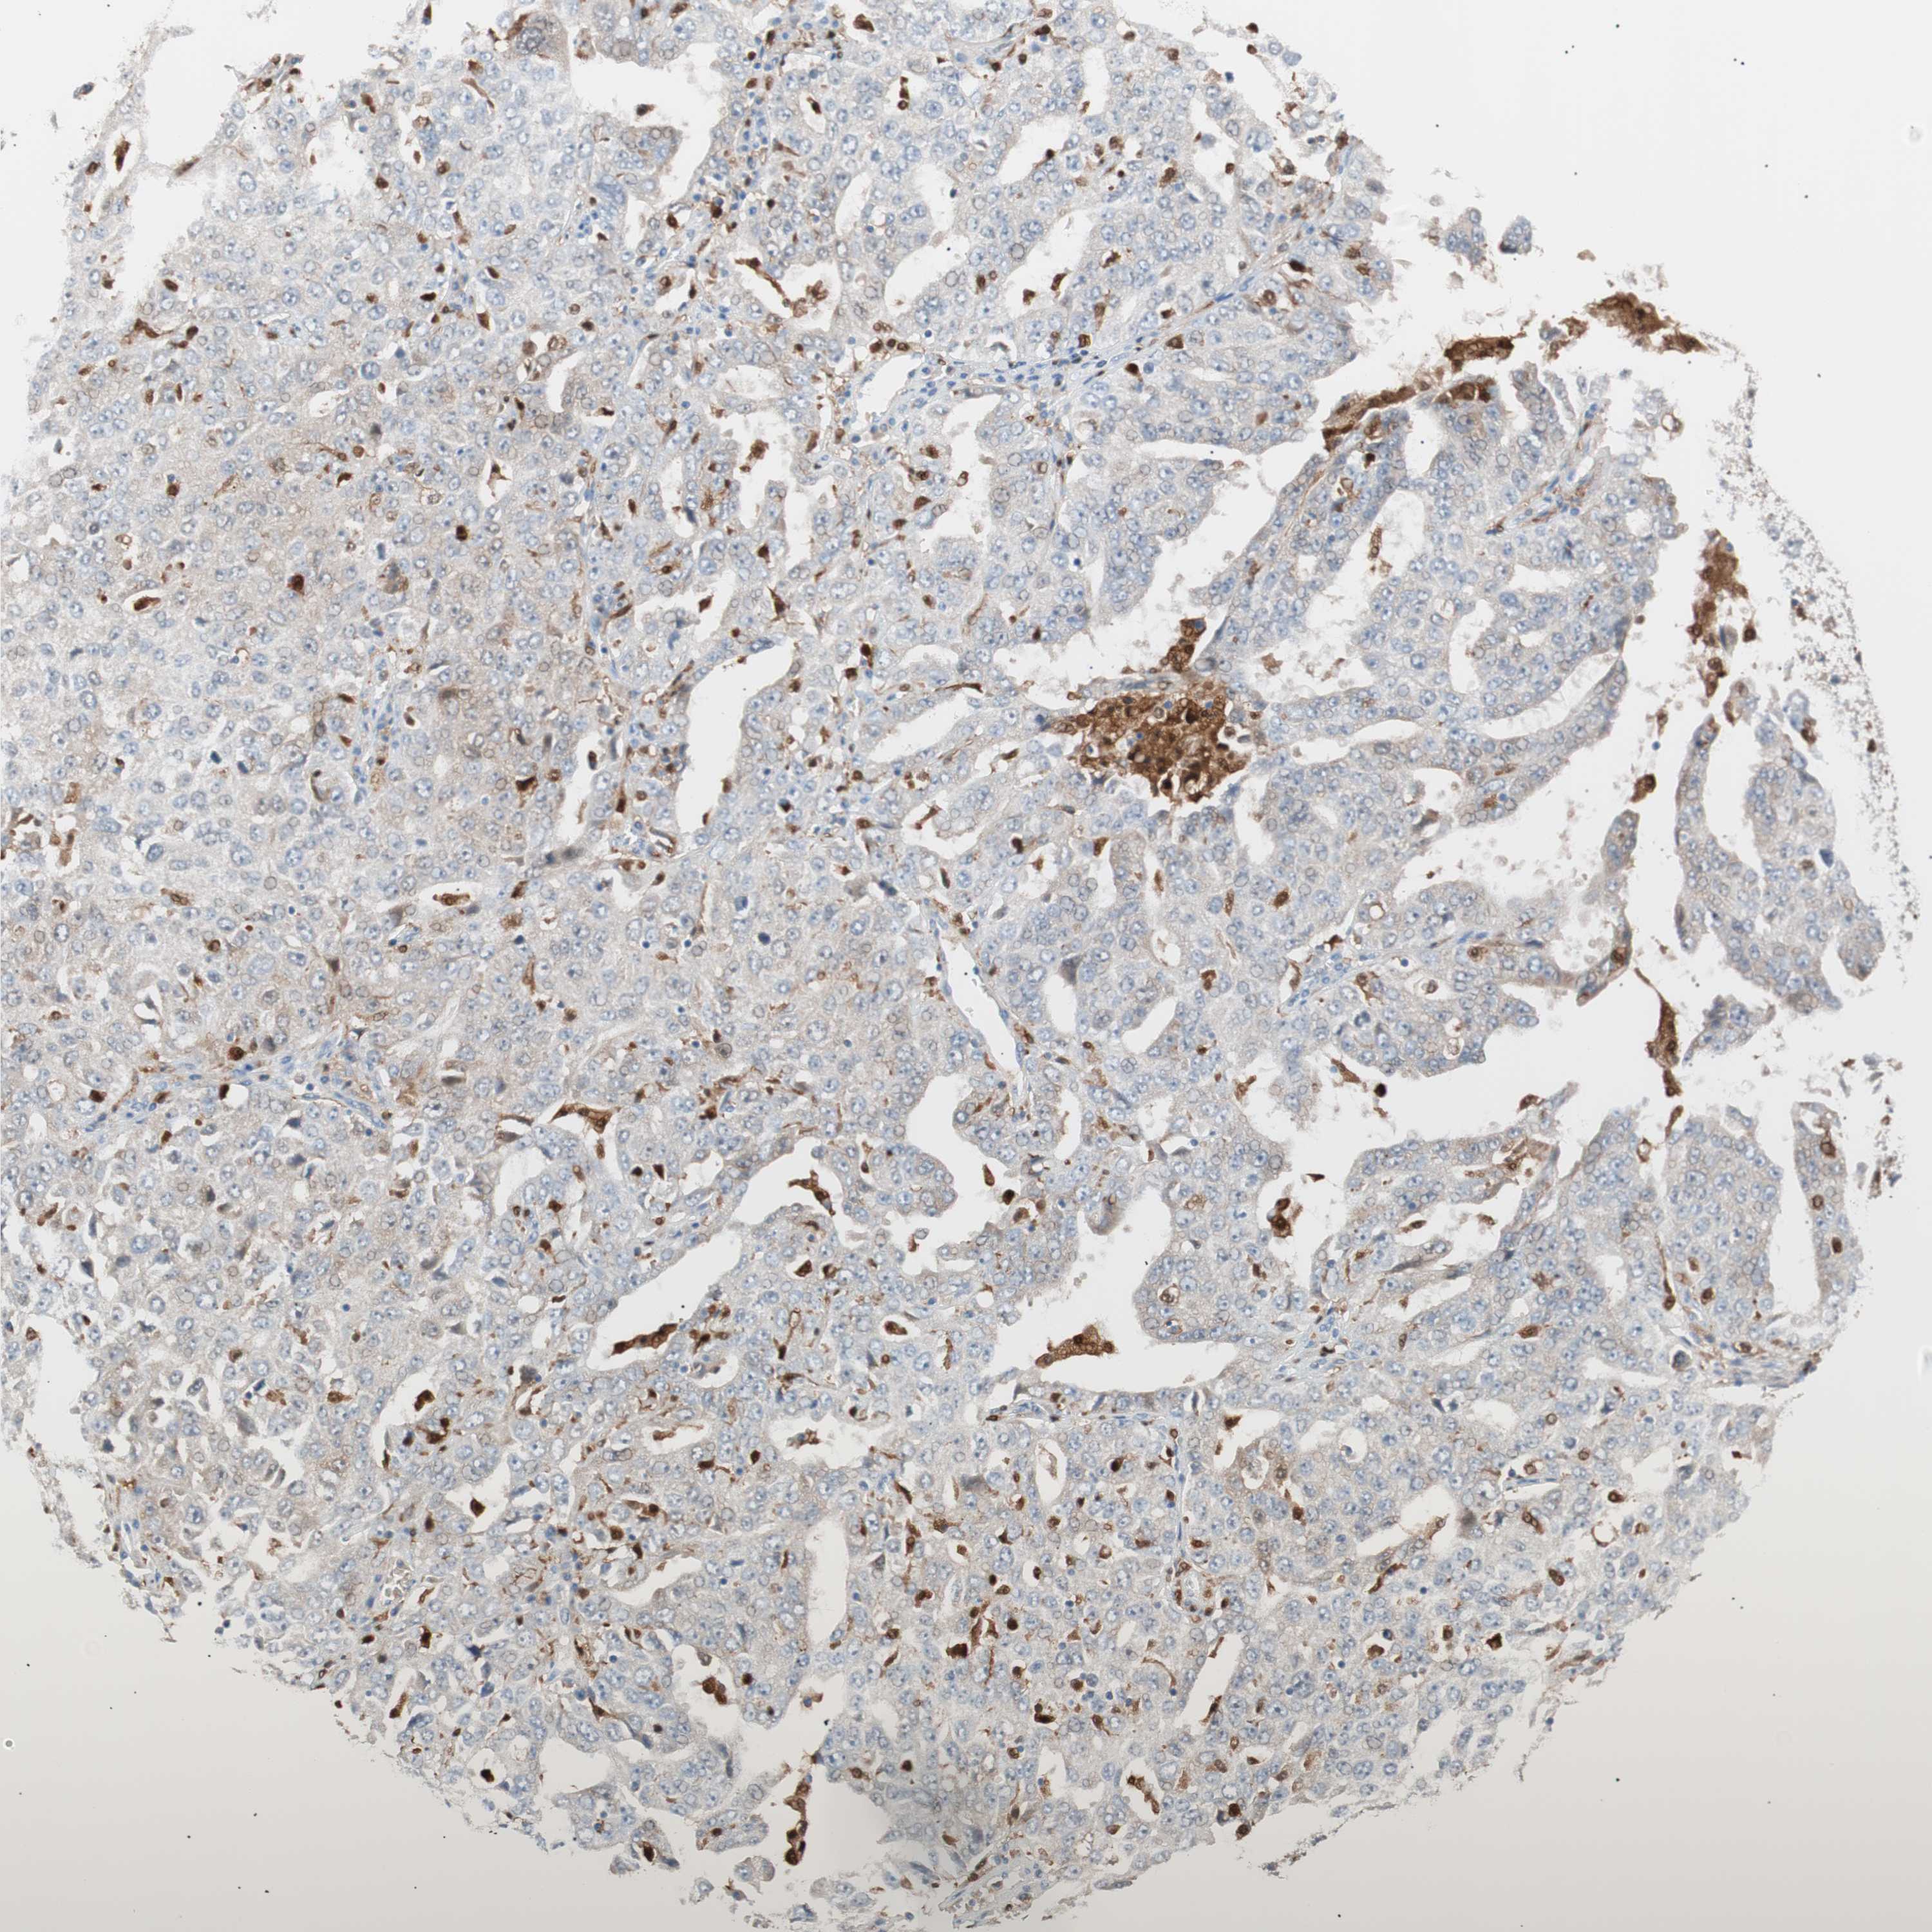

OVARIAN CANCER - Protein expressioni

A mouse-over function shows sample information and annotation data. Click on an image to view it in a full screen mode. Samples can be filtered based on level of antibody staining by selecting one or several of the following categories: high, medium, low and not detected. The assay and annotation is described here.

Note that samples used for immunohistochemistry by the Human Protein Atlas do not correspond to samples in the TCGA dataset.

Antibody stainingi

Antibody staining in the annotated cell types in the current human tissue is reported as not detected, low, medium, or high, based on conventional immunohistochemistry profiling in selected tissues. This score is based on the combination of the staining intensity and fraction of stained cells.

Each image is clickable and will lead to virtual microscopy that enables deeper exploration of all samples and also displays staining intensity scores, fraction scores and subcellular localization as well as patient and tissue information for each sample.

Antibody HPA003980

Antibody CAB007772

Staining

High

Medium

Low

Not detected

Intensity

Strong

Moderate

Weak

Negative

Quantity

>75%

75%-25%

<25%

None

Location

Nuclear

Cytoplasmic/membranous

Cytoplasmic/membranous,nuclear

Carcinoma, endometroid

Carcinoma, NOS

Cystadenocarcinoma, serous, NOS

Cystadenocarcinoma, mucinous, NOS